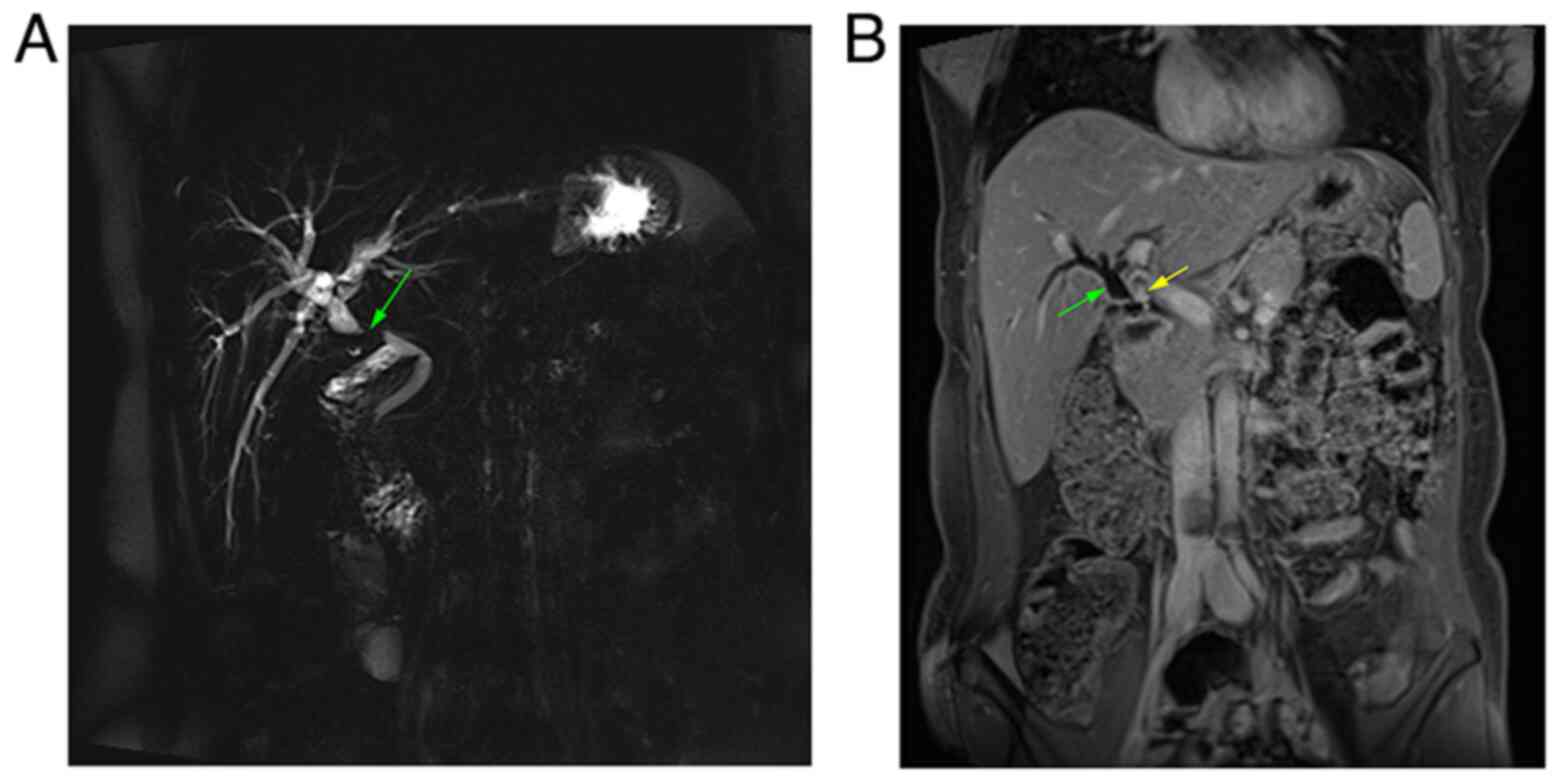

The analyses of blood parameters, including white blood cell count, serum creatinine, blood urea, C-reactive protein, serum amylase, carcinoembryonic antigen and CA 19-9 levels, revealed results within the normal range. The liver function profile was elevated (total serum bilirubin was 4.2 mg/dl and alkaline phosphatase was 250 IU/l). Magnetic resonance cholangiopancreatography (MRCP) revealed a dilated proximal bile duct and mild dilatation of the intrahepatic biliary tree due to a 1-cm stricture, 16 mm distal to the confluence of the right and left hepatic ducts (Fig. 1). Dynamic liver magnetic resonance imaging (MRI) was performed to exclude tumors, and it revealed the same finding of bile duct stricture due to a clip on the bile duct. Based on this finding, the case was diagnosed as a post-operative bile duct stricture. An endoscopic retrograde cholangiopancreatography (ERCP) was initially planned to be conducted.

Figure 1

(A) Magnetic resonance cholangiopancreatography thick slab illustrating intrahepatic biliary dilatation with upper common bile duct stricture (green arrow). (B) Abdominal magnetic resonance imaging with intravenous contrast coronal section, illustrating biliary dilatation (green arrow), and a small enhanced lesion at the site of biliary obstruction (yellow arrow).

The most difficult aspect of the management of biliary traumatic neuroma is the pre-operative diagnosis (13). Although various imaging techniques, such as ultrasound (US), computed tomography (CT) and MRI, are useful to some extent, the diagnosis of biliary traumatic neuroma pre-operatively remains challenging (16,17). Typically, these tumors are found following the compression of the surrounding structures, leading to the misdiagnosis as hilar cholangiocarcinoma (13). Previous studies have observed that CT and MRI clearly demonstrate biliary duct dilatation without proof of a tumor-like lesion (18,19). MRCP can reveal bile duct stenosis (18). However, none of these modalities has the sensitivity and specificity required for proper pre-surgical identification of biliary traumatic neuroma, and none can definitively rule out the existence of malignancy (13). In the case described in the present study, MRCP revealed a dilated proximal bile duct and mild dilatation of the intrahepatic biliary tree due to a stricture distal to the confluence of the right and left hepatic ducts. A dynamic liver MRI was performed to exclude tumors and revealed the same finding of bile duct stricture due to a clip on the bile duct.